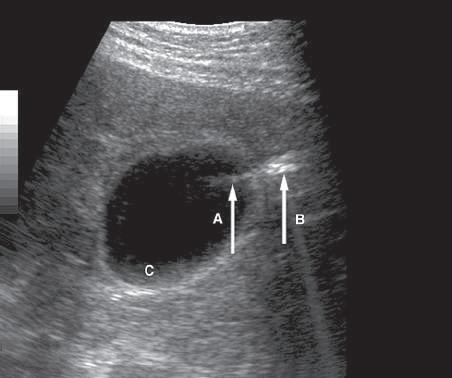

FIG. 1.29 Side Lobe Artifact. Transverse image of the gallbladder reveals a bright internal echo (A) that suggests a band or septum within the gallbladder. This is a side lobe artifact related to the presence of a strong out-of-plane reflector (B) medial to the gallbladder. The low-level echoes in the dependent portion of the gallbladder (C) are also artifactual and are caused by the same phenomenon. Side lobe and slice thickness artifacts are of clinical importance because they may create the impression of debris in fluid-filled structures.

in what is actually a simple ovarian cyst.